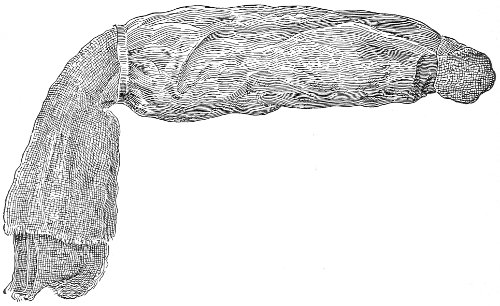

Fig. 10.—The Sims position.

The Sims position, which is also called the latero-abdominal position, is shown in Fig. 10. The woman is placed on the bed or table upon her left side. The side of the face is upon the pillow; the left arm is behind the back, so that the left breast rests upon the table. The thighs are flexed upon the abdomen at an angle of about 90° to the trunk. The right thigh is more flexed than the left, so that the right knee may touch the table above the left knee. The legs are flexed on the thighs. In this position there is a tendency for the intestines, following the force of gravity, to fall from the pelvis, 32 and for the uterus and other pelvic viscera to be drawn up. When the perineum is retracted with the blade of the Sims speculum, air will enter the vagina and the vaginal slit will become distended (Fig. 11). To facilitate inspection of the cervix it is usually necessary also to push forward the anterior abdominal wall by some kind of depressor, such as the one shown in Fig. 8.